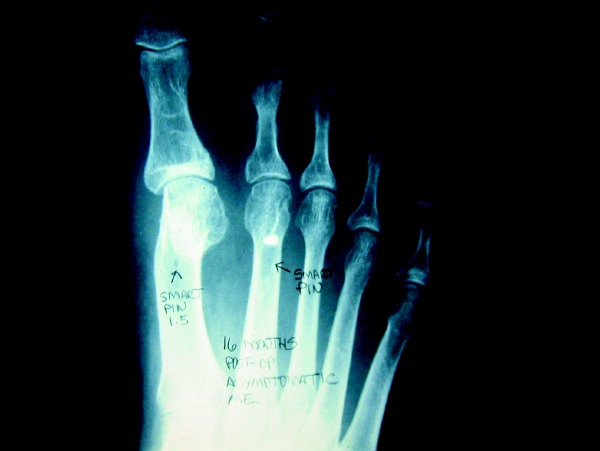

A Few Thoughts On Postoperative Management

Postoperative management will depend upon the procedures that clinicians perform. When one employs a Kirschner wire for stabilization, maintain it for at least three weeks or longer if possible to allow for sufficient fibrosis and tendon healing within the digit. Using AirCast™, a low-profile synthetic walker, has been proven to be an excellent way to allow the patient to remain ambulatory while eliminating the propulsive phase of gait and offloading the forefoot. I will also have the patient utilize the removable digital splint for six to eight weeks at night following the removal of all bandages and Kirschner wire. For a period of two months after surgery, I advise the patient to refrain from engaging in certain activities (such as walking up hills, walking on wet sand, squatting to perform gardening, etc.) that will create extreme dorsiflexion of the second MTPJ.